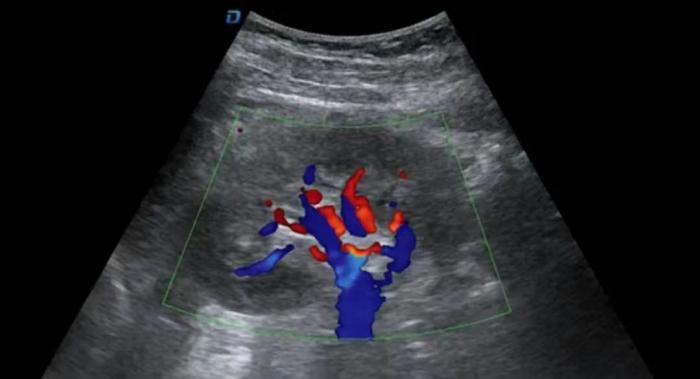

在做检查时,经常会有人问,“医生,不是彩超吗,怎么屏幕显示的是黑白的?”这跟我们家里的彩色电视机是不一样的。彩超指的是彩色多普勒超声检查,彩超中的彩色一般有红色和蓝色两种,为了提示血管内血流的方向,医生通过血流方向判断目标脏器是否有血供以及血流方向以协助诊断疾病,而我们经常看到的黑白的就是二维超声,是现在超声诊断的主要方法。所以说,彩超是彩色的,但是不等同于家里的彩色电视机。